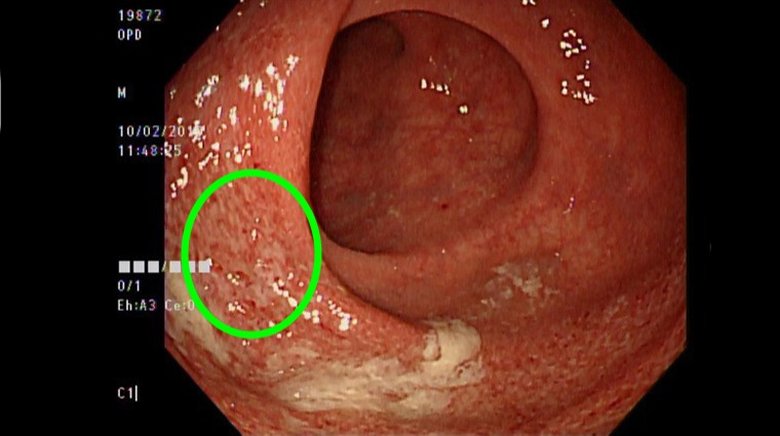

潰瘍性結腸炎是1種慢性、反覆性腸道發炎疾病,目前致病機轉不明,推測可能與遺傳、免疫系統失調、腸道共生菌失衡、飲食、壓力等因素有關。(圖/亞洲大學附屬醫院提供)

張家熙指出,潰瘍性結腸炎是1種慢性、反覆性腸道發炎疾病,目前致病機轉不明,推測可能與遺傳、免疫系統失調、腸道共生菌失衡、飲食、壓力等因素有關,好發於20歲左右年輕人,以及50至60歲中年人,通常會出現持續腹瀉、嚴重腹痛、解血便和黏液便,伴隨體重減輕、發燒等症狀,並可能造成腸道出血、腸道穿孔,增加罹患大腸癌機率等併發症。

醫師也表示,潰瘍性結腸炎症狀類似腸躁症,都可能出現腹痛腹瀉、排便情況與型態改變、糞便帶有黏液或帶血等症狀,常與情緒和壓力有關,在鑑別2項疾病時,需要透過綜合病史、臨床表現、抽血和糞便檢驗、大腸鏡檢查合併組織病理切片方能確診。治療方面,針對輕度患者,會使用抗發炎藥物治療,降低發炎對腸道造成的破壞,而重度患者,則會使用針劑類固醇合併抗發炎藥物或免疫調節劑,若仍然無效,就須透過生物製劑治療,以協助修復腸黏膜,降低未來癌化的風險。